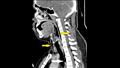

وكشفت الأشعة السينية أنه يعاني من انتفاخ الرئة الجراحي، عندما ينحصر الهواء في أعمق الأنسجة تحت الجلد.

وأظهرت الأشعة المقطعية أن التمزق كان بين العظمتين الثالثة والرابعة من رقبته وأن الهواء يتراكم في الفراغ بين الرئتين في صدره.